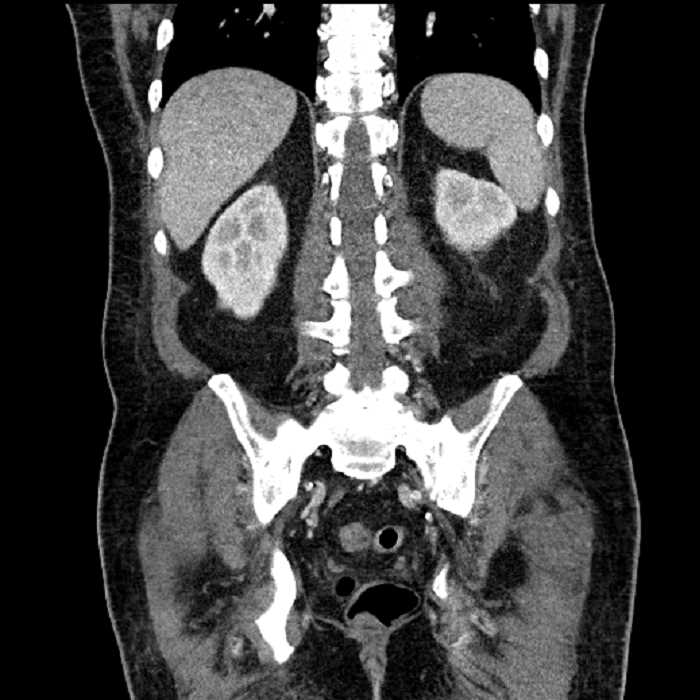

Age: 63

Sex: Male

Indication: Abdominal pain

• Large fluid density structure in hepatic segments 7 and 8 measuring 10 x 7 x 7 cm with internal septation and circumferential ill-defined low density compatible with edema

• Peripherally enhancing subcapsular collections along the anterior margin of the left hepatic lobe measuring 3 x 1 cm and 2 x 1 cm

• Clearly marginated fluid density structure in segment 7 and several other scattered tiny hypodensities, which likely represent cysts

• Hepatic abscess

Acute sigmoid diverticulitis complicated by a small contained perforation and a large abscess in the right hepatic lobe. Additional small subcapsular abscesses along the anterior margin of the left hepatic lobe.

• The classic CT imaging appearance is a double target sign with internal low density surrounded by an internal enhancing rim (capsule) and a low density external rim (edema)

Hepatic abscess showing the double target sign with low density internally surrounded by a thin inner enhancing rim (red arrow) and ill-defined outer low density rim (yellow arrow). Blue arrow indicates an internal septation. Red arrows: additional smaller subcapsular abscesses. Red arrow: focal contained perforation associated with diverticulitis.